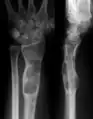

Clinical and radiological evaluations are conducted in order to detect the presence of bone neoplasms or lesions typically found in Ollier disease. Histological evaluations are mainly used to examine or detect malignancies.

Abnormal bone growth such as shortening or thickening and deformity may be observed in patients of Ollier disease. These bone lesions are visible at birth using radiography but are usually not screened or examined for until clinical manifestations present during early childhood. However, some patients may exhibit no signs of any symptoms.[1] One study found thirteen to be the mean age of diagnosis in patients with Ollier disease. In a roentgenogram, there would normally be the presence of several homogeneous lesions of an oval or elongated shape with bone edges that are slightly thickened.[3] With age, these lesions may calcify and appear as diffusely minute spots or stippled. Fan-like septations or streaks would be indicative of the presence of several enchondromas. Early detection and consistent and repeated monitoring is important in order to prevent and treat any potential bone neoplasms.

Magnetic resonance imaging (MRI), ultrasound, and scintigraphy are generally not practical for diagnostic purposes. X-rays are not as effective in the monitoring or evaluation of enchondromas due to frequent localized changes also sometimes due to the large number of enchondromas. MRI can sometimes however be used to monitor and evaluate symptomatic lesions in the case of potential malignant transformations.

X-ray showing enchondromas localized in the lower part of the radius of a 37-year-old patient affected with Ollier disease -